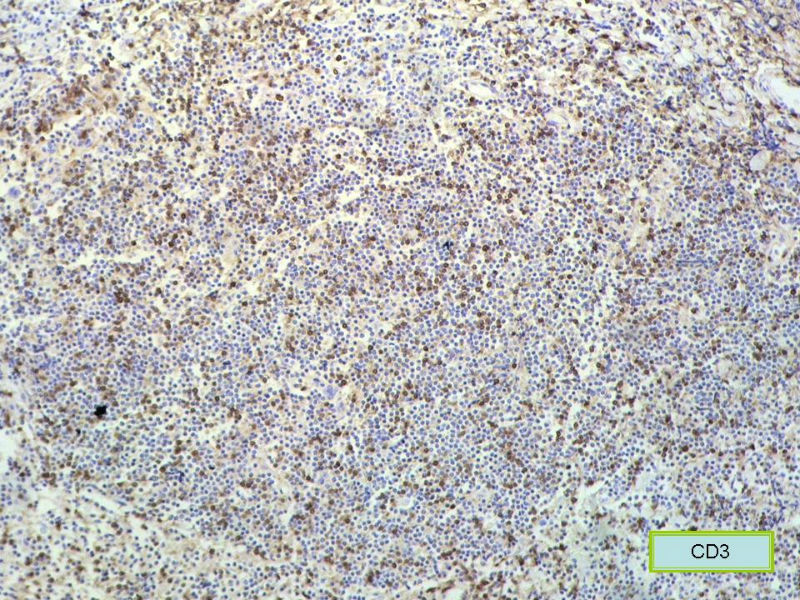

赞成以上专家的讨论,根绝病史,HE形态考虑小细胞病变,CD3、CD5散在+,还是倾向淋巴造血系统病变,CD20、CD79a阳性不明确,可以考虑复查,加做PAX-5,核阳性容易判断,另再加做鉴别其它小细胞肿瘤的抗体:CD99、CD43、CyclinD1、CK、CgA、Syn等,了解病史:骨髓、末梢血、肝、脾等。

请再标记CD20和CD79a!图片中阳性不明确,根据T细胞标记看,应该是B细胞结节。Ki67散而少,不支持低级别滤泡性淋巴瘤,若B细胞弥漫阳性,则是惰性B细胞非霍奇金淋巴瘤,首先考虑套细胞,然后是边缘区淋巴瘤。不做生发中心标记,Bcl-2在小B细胞淋巴瘤分类中无意义。

淋巴样细胞。细胞形态单一,细胞小。主要鉴别:

1)粘膜相关淋巴组织淋巴瘤

2)小细胞性淋巴瘤/慢性淋巴细胞性白血病

3)套细胞淋巴瘤